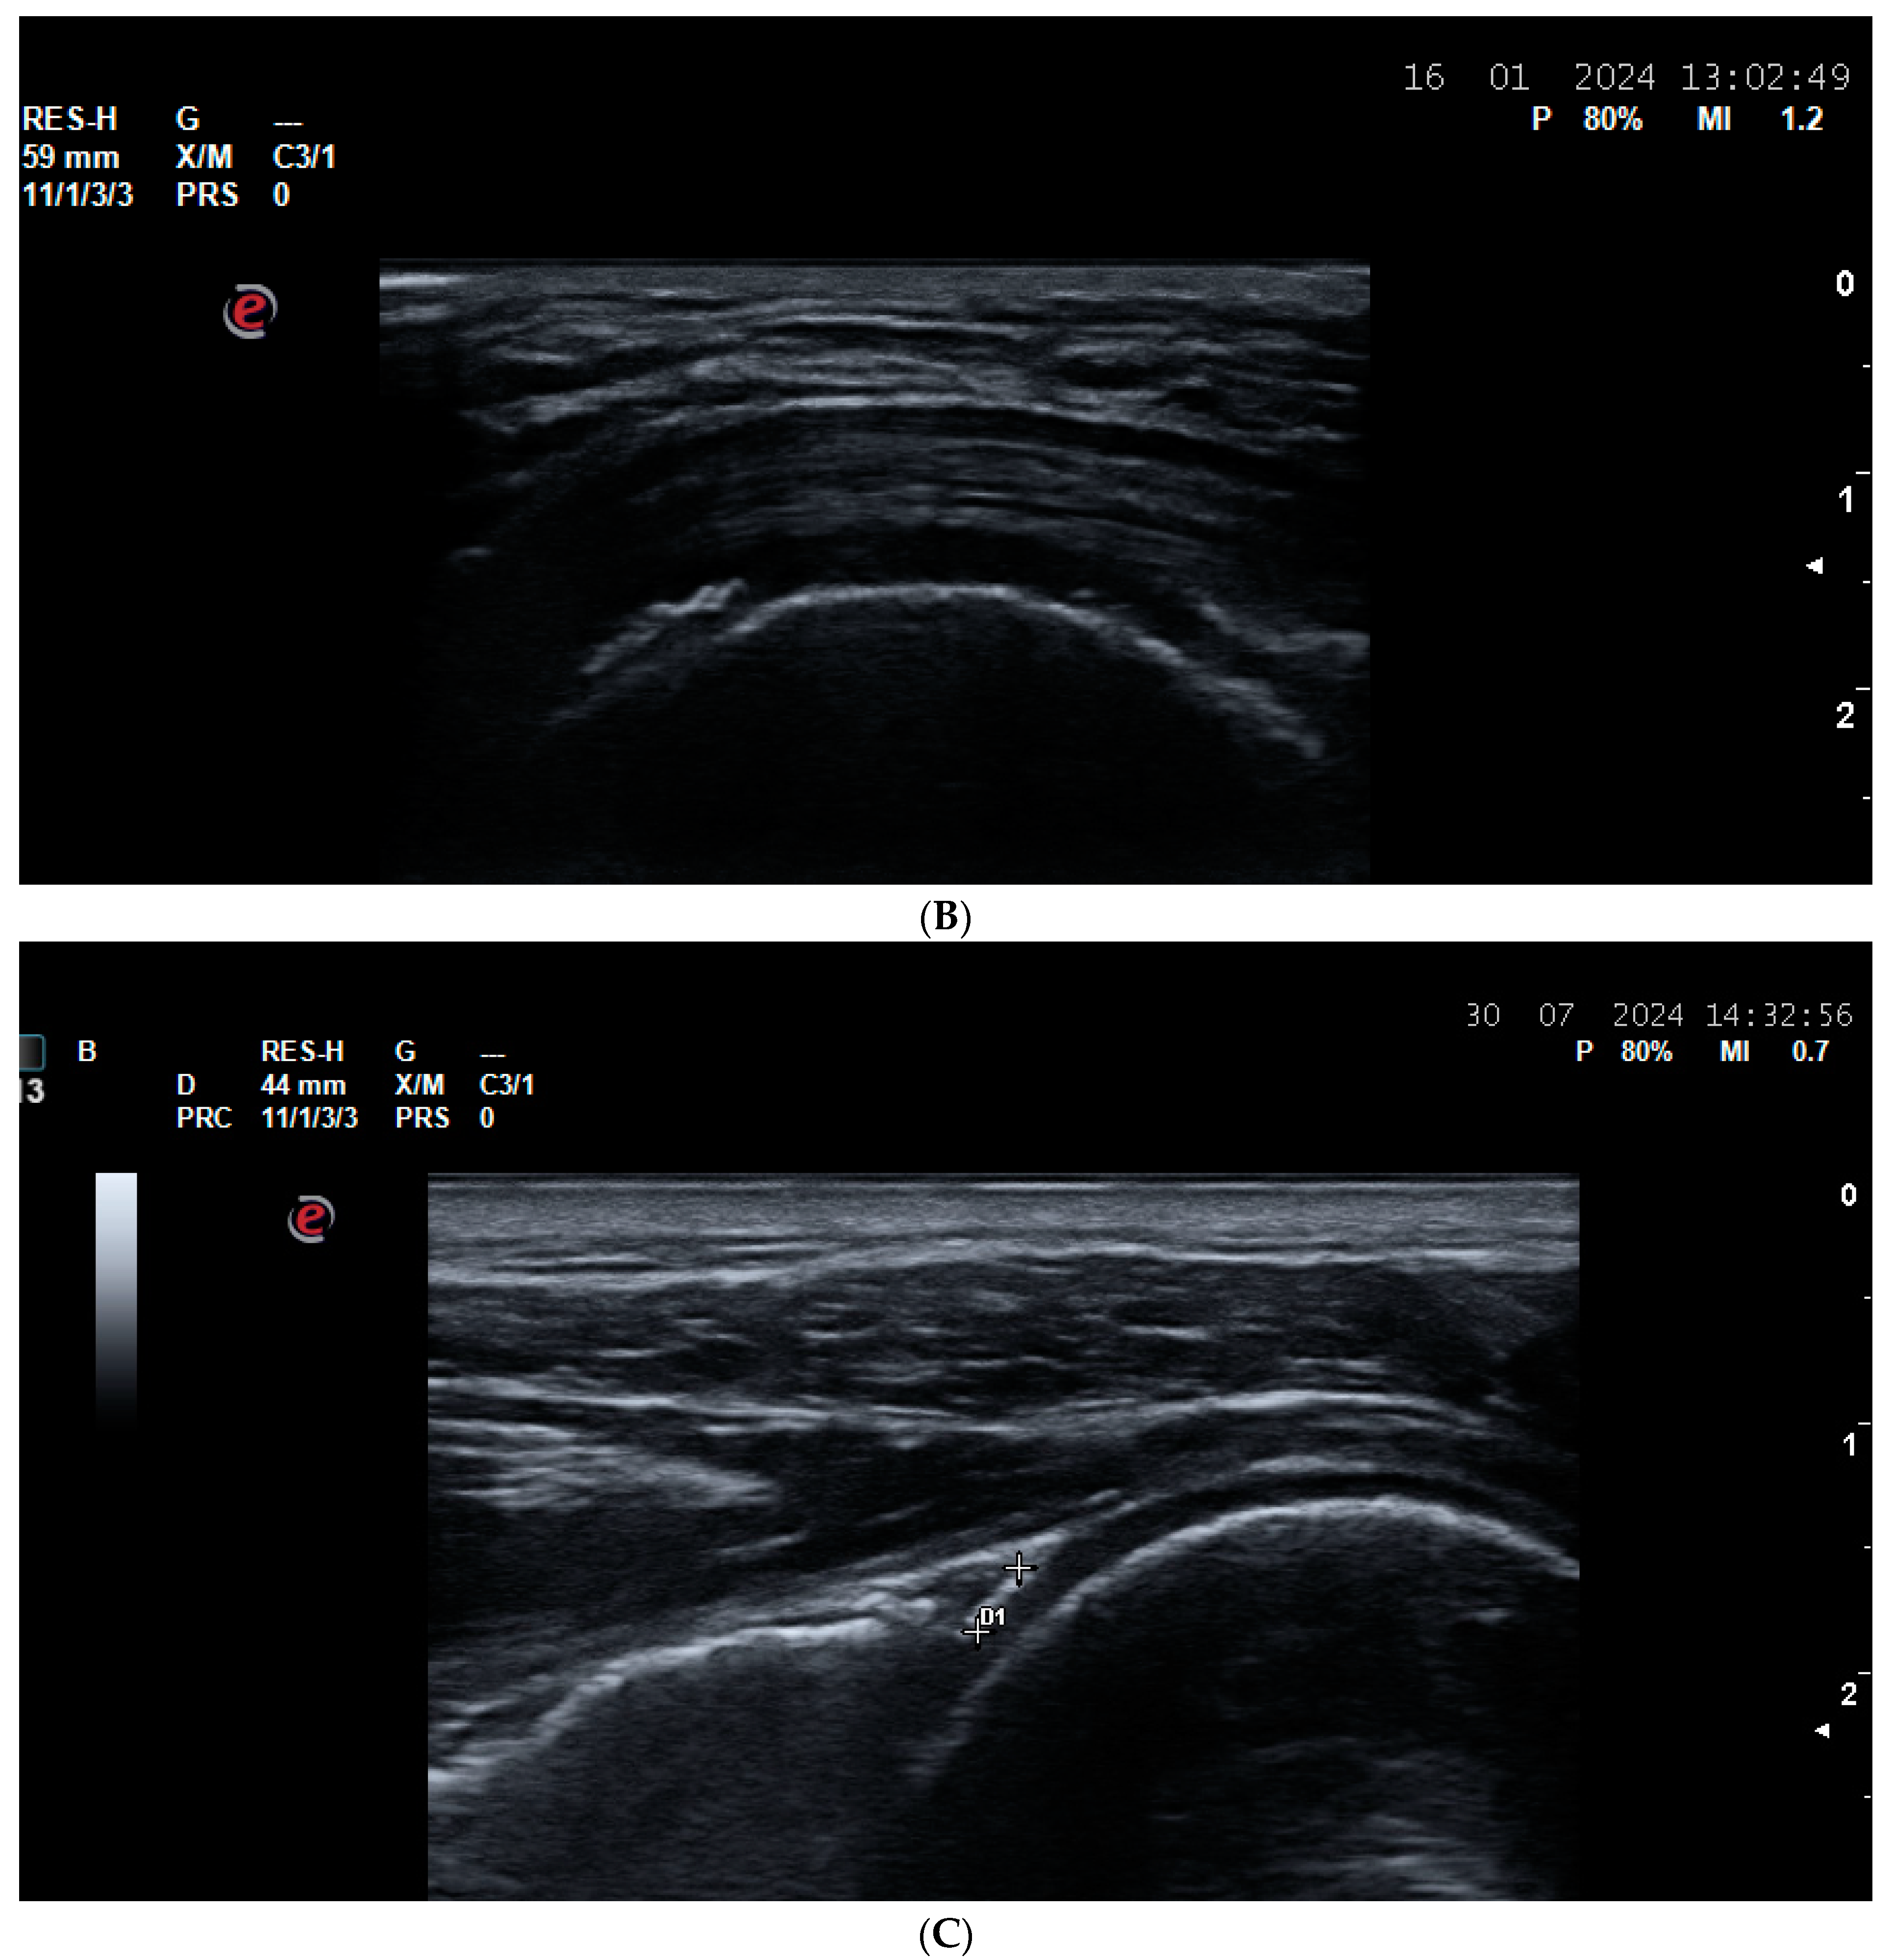

5.2. Vasculitides

- Schmidt, W.A.; Schäfer, V.S. Diagnosing vasculitis with ultrasound: Findings and pitfalls. Ther. Adv. Musculoskelet. Dis. 2024, 16, 1759720X241251742. [Google Scholar] [CrossRef] [PubMed] [PubMed Central]

- Dejaco, C.; Ramiro, S.; Bond, M.; Bosch, P.; Ponte, C.; Mackie, S.L.; Bley, T.A.; Blockmans, D.; Brolin, S.; Bolek, E.C.; et al. EULAR recommendations for the use of imaging in large vessel vasculitis in clinical practice: 2023 update. Ann. Rheum. Dis. 2024, 83, 741–751. [Google Scholar] [CrossRef] [PubMed]

- Schmidt, W.A. Monitoring giant cell arteritis with ultrasound. Rheumatology 2023, 62, 2948–2950. [Google Scholar] [CrossRef] [PubMed]